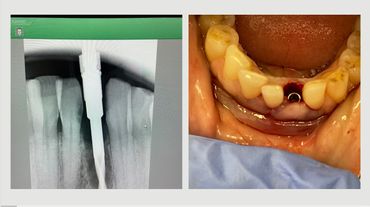

Conventional and Guided in one Kit

Where and how to use 2.9 Narrow implant